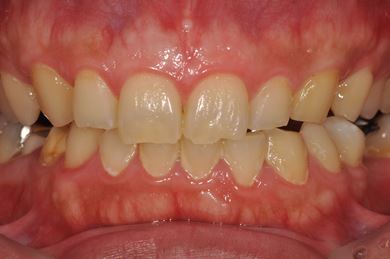

インプラントの症例写真 IMPLANT

インプラント治療+セラミック治療

| 性別/年齢 | 男性 / 32歳 | ||||||||||||||||||||||||||||||||

| 主訴 | 何ヵ所か虫歯が進行してしまったので治療をして欲しい。以前抜歯をした所についてはインプラントを希望する。 | ||||||||||||||||||||||||||||||||

| 治療内容 | インプラント1本、ハイブリッドセラミック4本、ハイブリッドセラミックインレー1本、歯肉歯槽骨整形 | ||||||||||||||||||||||||||||||||

| 総治療費 | 756,525円 | ||||||||||||||||||||||||||||||||

| 治療期間 | 8ヶ月 |